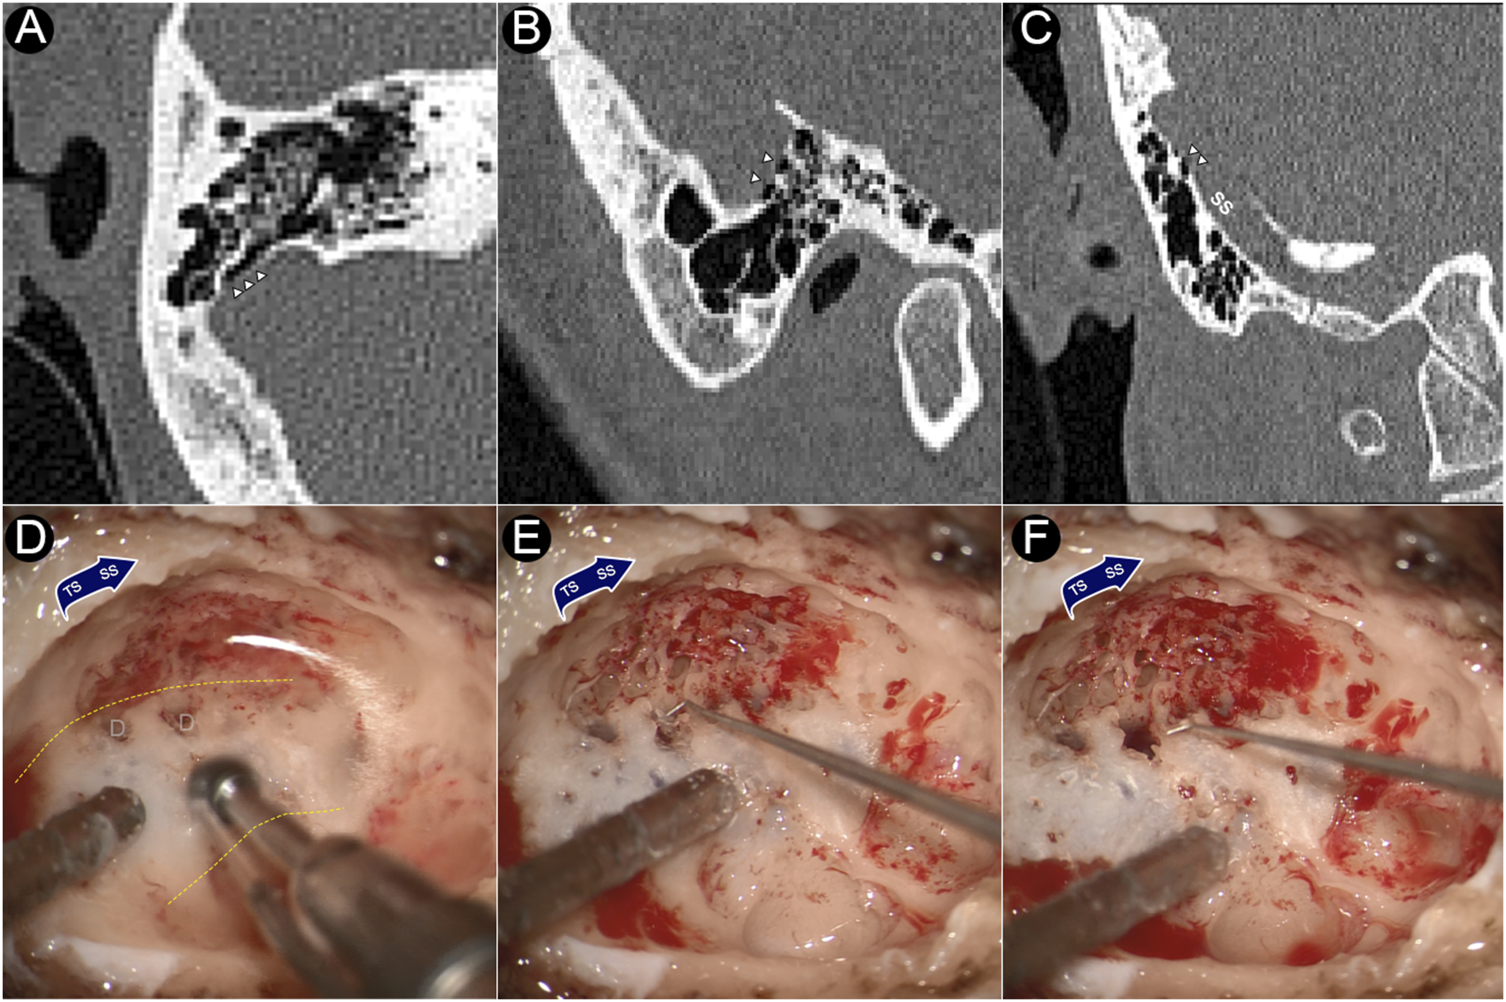

Intraoperative photographs and CT images of the dehiscence are shown in Figure 1. During the transtemporal surgery, the sigmoid sinus plate dehiscence was gradually exposed during the skeletonization of sigmoid sinus. After the mastoid air cells and osseous structures adjacent to the dehiscence were removed, the sigmoid sinus cortical plate and dehiscence was exposed. The bony structure overlying the vessel wall was deliberately preserved to prevent damage to the dehiscent bone tissue. The dehiscent plate was then harvested by separating the bone structure from the surrounding osseous wall and tissues underneath using a rectangular bone-burring pathway. The removed dehiscent sigmoid plate was immediately collected, placed in a fixative 4% paraformaldehyde solution for 24 h, and immersed in a solution of 75% alcohol for dehydration.

FIGURE 1

CT images and intraoperative photographs of the participant with sigmoid plate dehiscence. (A) Axial plane of dehiscence; (B) sagittal plane of dehiscence; (C) coronal plane of dehiscence. (D) Dehiscence exposed during skeletonization of sigmoid sinus. (E) Harvesting the dehiscent sigmoid plate. (F) After the removal of the dehiscent sigmoid plate. Triangles indicate the location of dehiscence. D represents dehiscence. Yellow dashed lines indicates the silhouette of the sigmoid sinus.